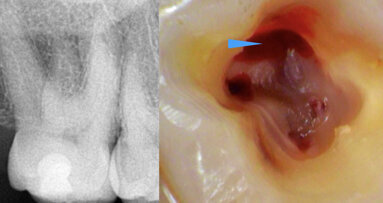

Maksilarni drugi molari su uvek izazov za endodontsku terapiju kanala korena zuba. Ove poteškoće su povezane sa lokacijom zuba, u maksili sa ograničenim...